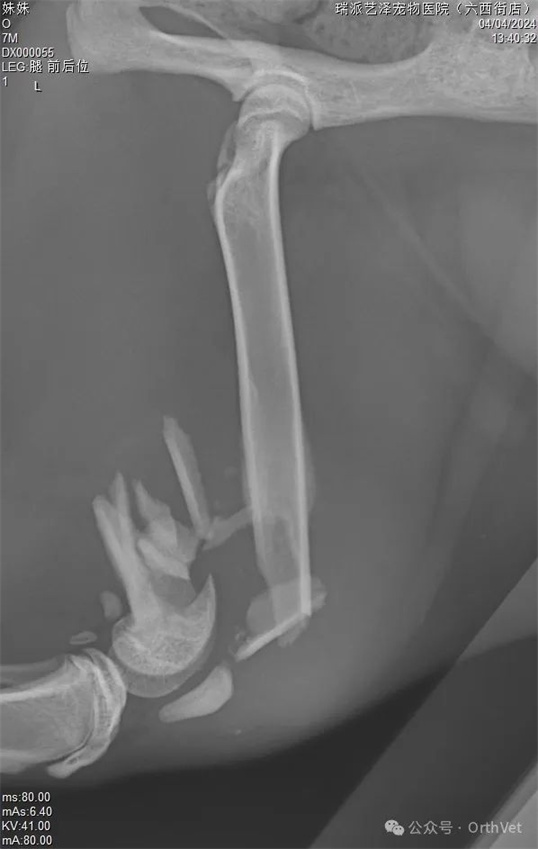

The above are preoperative X-rays